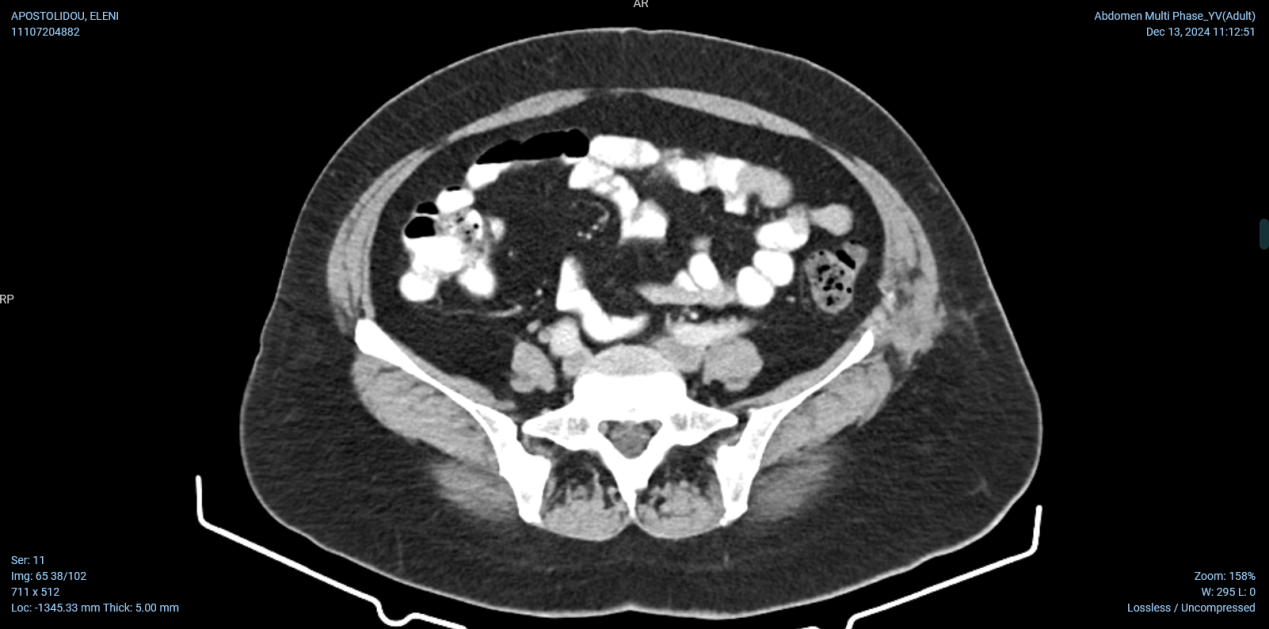

CT κοιλίας με σκιαγραφικό που αναδεικνύει το λεπτό έντερο στο κέντρο της κοιλίας εντός παχέος ινώδους υμένα (Ευγενική παραχώρηση Dr. V. Penopoulos)